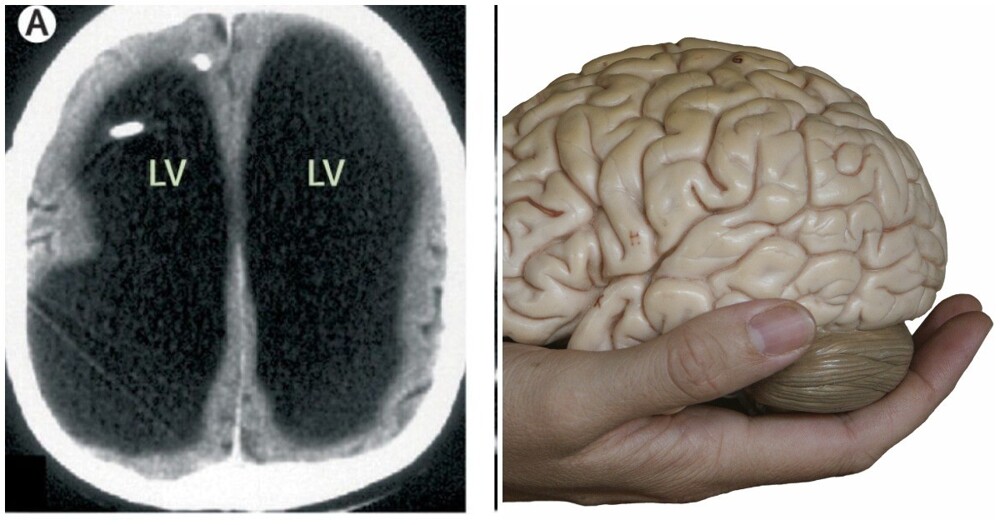

In a 44-year-old man, the skull was full of fluid, and from the brain only the thinnest layer of brain tissue remained. He did a brain scan for the first time and did not even suspect that something was wrong with him.

Scientists zealously undertook to investigate the patient and came to the conclusion that that his brain was slowly being destroyed in a process called dropsy of the brain, or, in scientific terms, hydrocephalus. Diagnosis the man was put in as a teenager and had a bypass, to restore the movement of cerebrospinal fluid.

But at the age of 14, the shunt was removed and the brain began to gradually die off, as the fluid continued to accumulate in it.